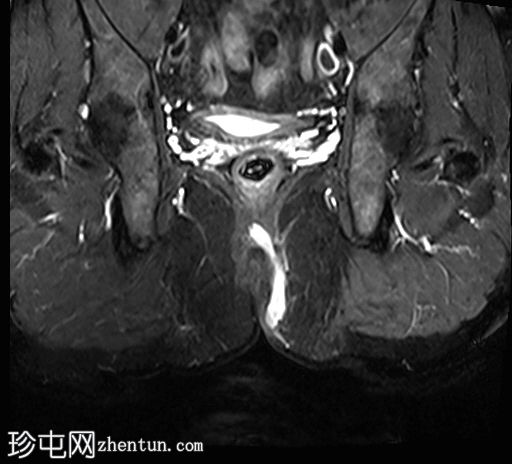

冠状位

T1时间

位于5点钟和6点钟位置之间,在STIR和T2加权图像上呈高信号。

瘘管起源于括约肌间平面附近,穿过肛门内外括约肌,并延伸至左侧坐骨肛门窝。瘘管内充满液体信号,周围有轻微水肿。肛提肌上方未观察到颅骨延伸。

根据圣詹姆斯大学医院的磁共振分类系统,该病例被归类为III级左侧肛周经括约肌瘘,左侧坐骨肛门窝可见炎症改变。